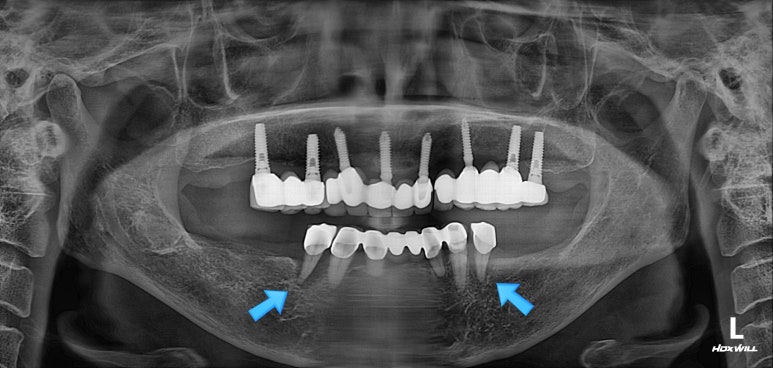

수술 후 촬영한 치과용 파노라마 사진에서, 정~말 깔끔하고 예쁘게 식립된 임플란트를 보실 수 있습니다.

아래턱뼈 내부에는 하치조신경이라는 감각신경이 주행하고 있는데요, 네비게이션 임플란트를 통해 수술 후 감각마비 없이 깔끔하게 마무리 되었습니다.

치과용 파노라마 사진을 보면 뭔가 좌우 대칭으로 깔끔하게 완성된 아래턱 양쪽 어금니 임플란트를 보실 수 있어요!!

Before & After

치과용 파노라마 엑스레이만 보아도, 임플란트 여섯개가 깔끔하게 제작된 것을 보실 수 있을겁니다.